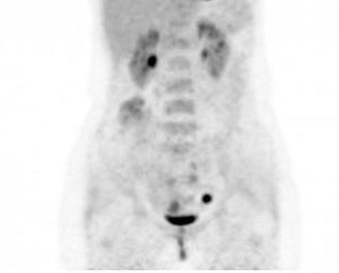

PET/CT:

我院病理會(huì)診:腺癌、Sliva A型;外院盆腔增強(qiáng):宮頸左后部可疑異常信號(hào)。腫瘤標(biāo)記物CA125 16.2U/ml、SccAg 1.0ng/ml;PET/CT:宮頸代謝增高灶1.8*1.3cm、SUVmax 3.7,余腹盆各部位未見明確異常增高病灶。患者無腹痛,為進(jìn)一步治療來我院,診斷 “宮頸腺癌IB1期”入院擬手術(shù)。患者病程中飲食、精神好,二便正常,體重?zé)o減輕。